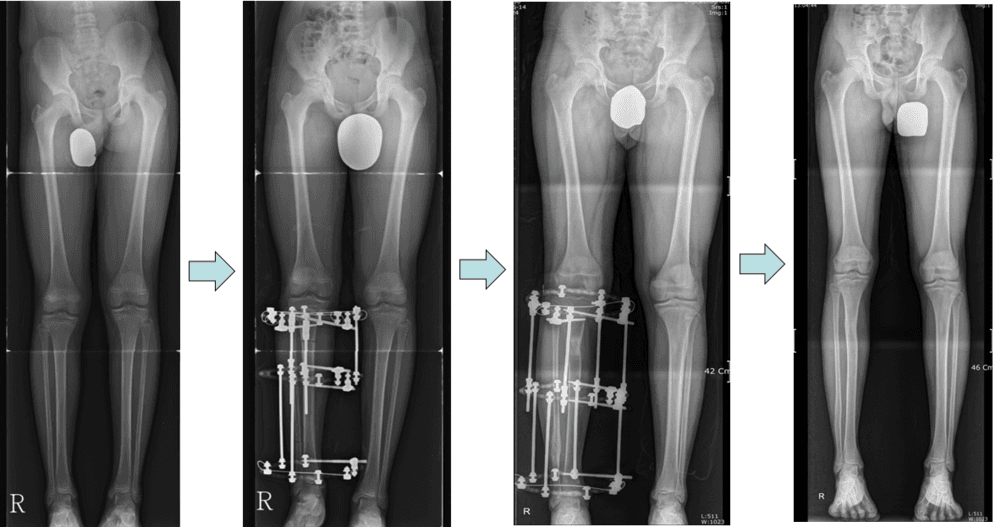

Femoral and Tibial Lengthening in Patient with Leg Length Discrepancy